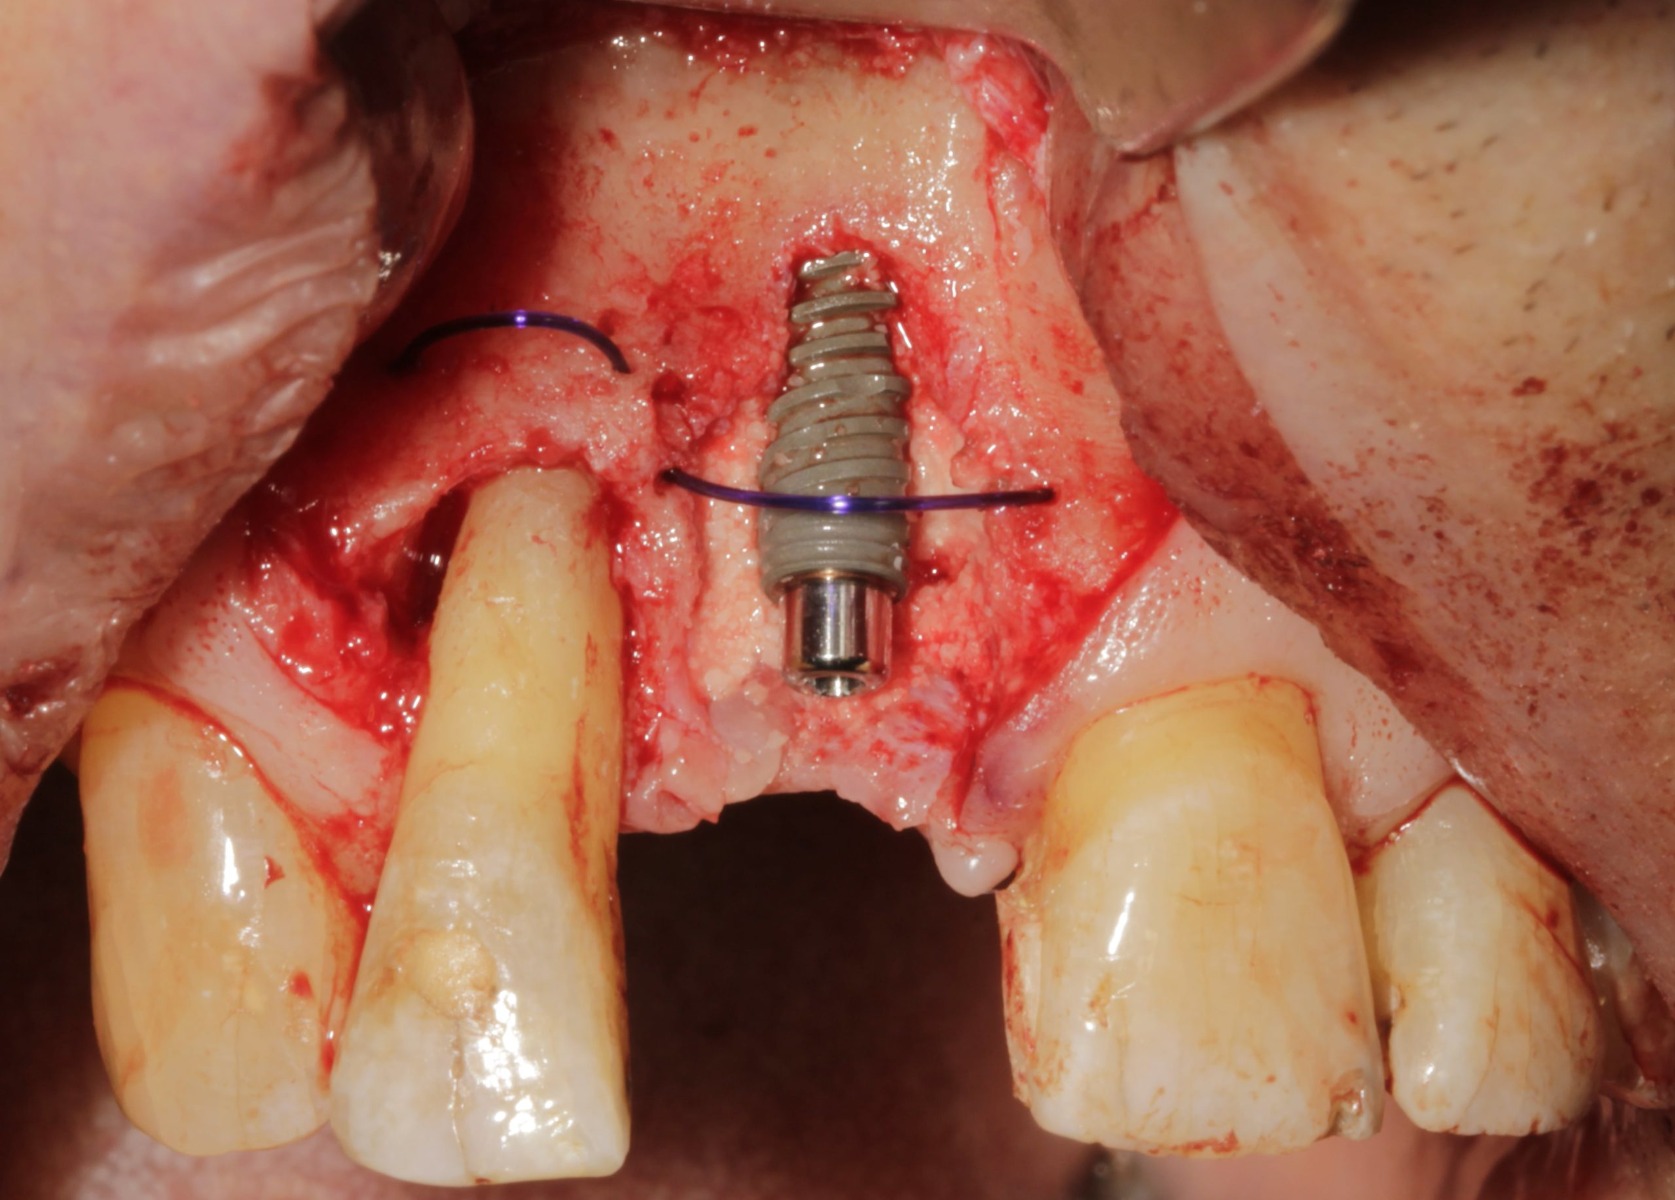

The ‘Tenting Technique’ is a method of using large, slowly resorbing sutures to stabilise graft material and aid retention of volume in dental implant surgery.

The tenting technique requires the positioning of short lengths of 2-0 PDS suture into the defect before grafting. This will create a ‘dome device’ capable of providing the required tensile strength and stability against soft tissue.

Complete by adding a wetter grafting solution to the site. Over time, the newly formed bone around the dental implant will resemble the host’s native bone.